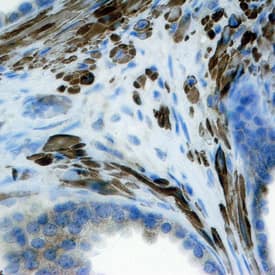

FGF-8 antibody in Human Prostate by Immunohistochemistry (IHC-P).

FGF‑8 in Human Prostate.

FGF-8 was detected in immersion fixed paraffin-embedded sections of human prostate using Mouse Anti-Human/Mouse FGF-8 Monoclonal Antibody (Catalog # MAB323) at 25 µg/mL overnight at 4 °C. Tissue was stained using the Anti-Mouse HRP-DAB Cell & Tissue Staining Kit (brown; Catalog # CTS002) and counterstained with hematoxylin (blue). Specific staining was localized to stromal cell cytoplasm. View our protocol for Chromogenic IHC Staining of Paraffin-embedded Tissue Sections.